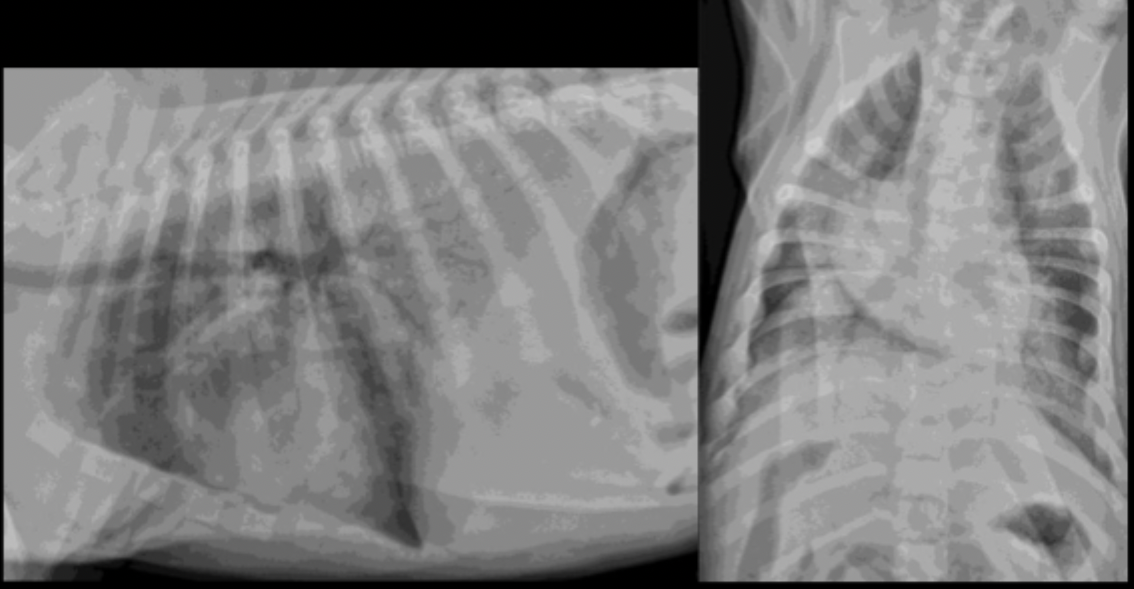

What can be seen in these cat radiographs?

Nothing, these radiographs are normal